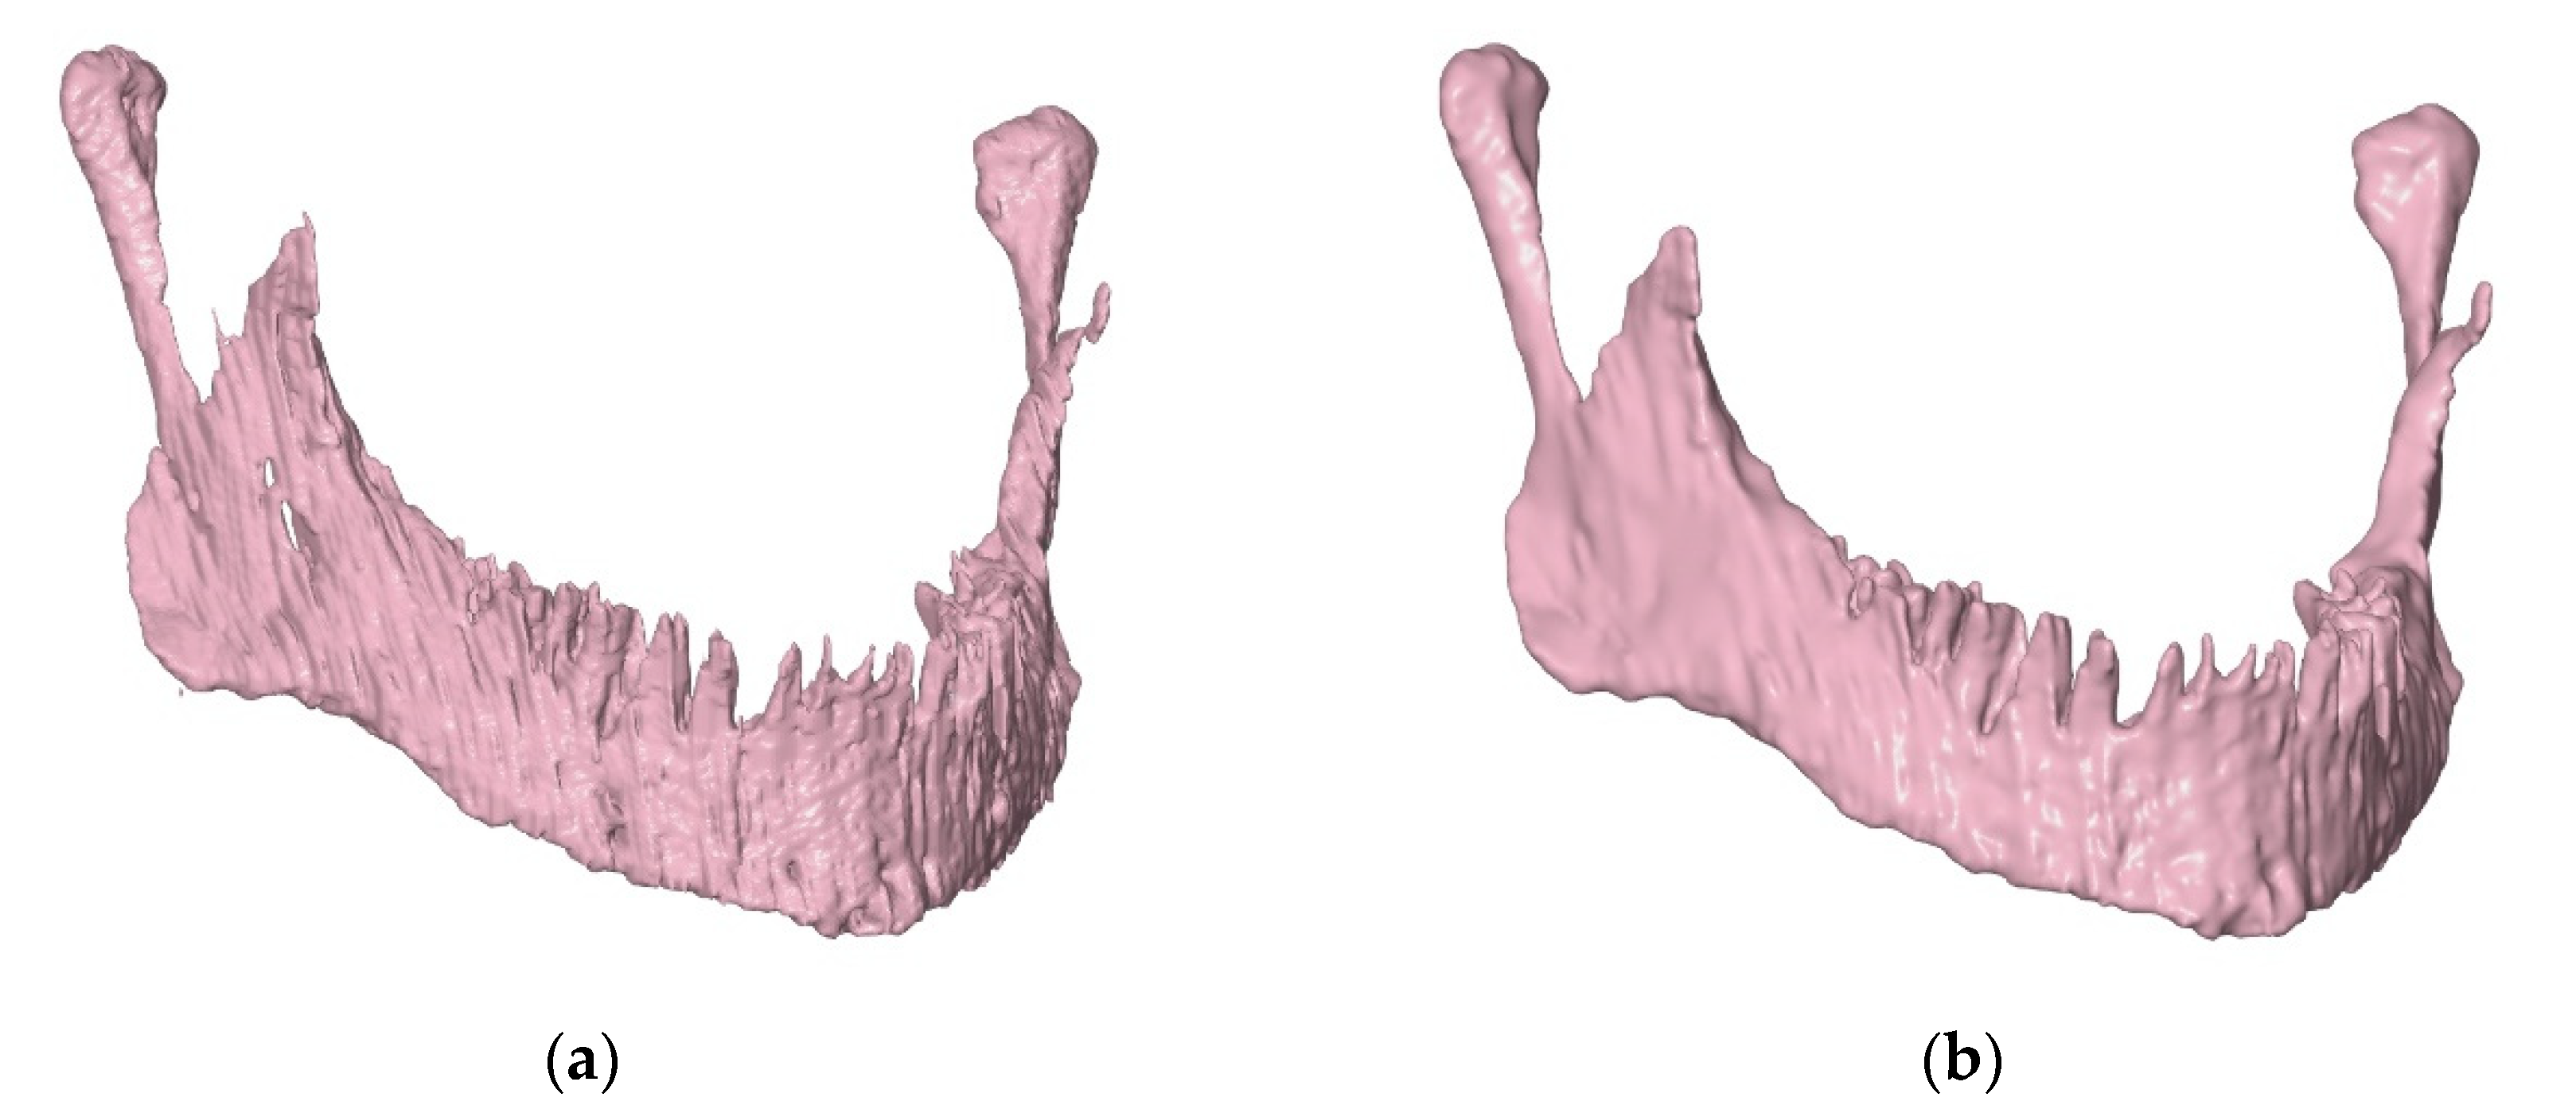

- Creation of an accurate model of the mandible together with the temporomandibular joint. The main assumption was to create a model that could be used for numerical analyses of various clinical cases, allowing the simulation of the work of fixing elements, assessment of the strength and durability of the fixation, and at the same time, without unnecessary simplifications, reflect real human anatomy. The input data were DICOM images obtained from medical imaging using computed tomography. Obtaining three-dimensional models of individual anatomical structures required the segmentation of tomographic images and then edition of the generated surface objects. Reverse engineering software for free modeling and a CAD program for parametric modeling were used.

2.3. Edition of STL Models